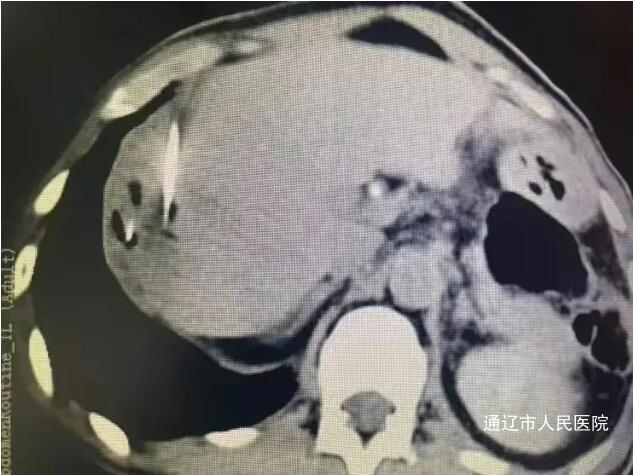

近日,我院肝胆胰外科成功实施了全市首例CT引导下肝肿瘤纳米刀消融术,标志着我院肝胆胰外科在肿瘤微创消融领域迈上新台阶,填补了本地区医疗技术空白。该患者男性,因腹胀于我院就诊,完善相关检查诊断结肠癌伴肠梗阻,肝占位性病变考虑转移瘤,讨论病情后决定一期行腹腔镜下根治性右半结肠切除术,术后复查腹部增强CT、增强肝脏MRI提示肝脏转移瘤有进展趋势,遂行CT引导下肝肿瘤纳米刀消融术。

手术过程中,患者行全身麻醉,在解放军总医院肖越勇教授指导下,我院肝胆胰外科主任医师郭雅明、手术麻醉科副主任医师高飞、CT室医护团队在CT引导下确认病灶位置并进针,确保电极区域完全包裹肿瘤后开始消融。消融过程中电流上升反馈良好,术后即刻增强CT显示消融范围覆盖病灶,周围血管、胆道结构完好无损伤,出现明显气体影,消融效果良好。消融完成后,退出穿刺针,手术顺利结束,术中麻醉效果满意,生命体征平稳,麻醉恢复后无腹痛腹胀,恶心呕吐等不适。术后给予对症支持治疗,患者恢复良好。和传统的消融治疗方式不同,纳米刀消融技术是通过脉冲电场导致细胞不可逆电穿孔,从而实现肿瘤组织杀伤,是一种非热选择性物理消融技术,可在实现消融肿瘤的同时,保留肿瘤周围的重要管道结构(血管、胆管和神经)完整性,并且无热沉效应,消融肿瘤细胞,适用于消融治疗靠近肝门、胆囊、膈肌和结肠等肝脏特殊部位的肿瘤有着独特的优势。纳米刀消融手术为现阶段先进、安全的肿瘤消融技术,它为无法使用传统手术方式的特殊部位癌症患者提供了新的治疗方式,还具有能够选择性消融,时间短、创口小等优点,一定程度上能够改善生活质量,延长生存时间,纳米刀消融对不能手术的肝癌、肺癌特别是胰腺癌具备较大的技术优势。此次全市首例纳米刀消融术的开展,标志我院微创介入技术取得重大突破,也为疑难肿瘤患者提供了更为先进技术的诊疗手段。